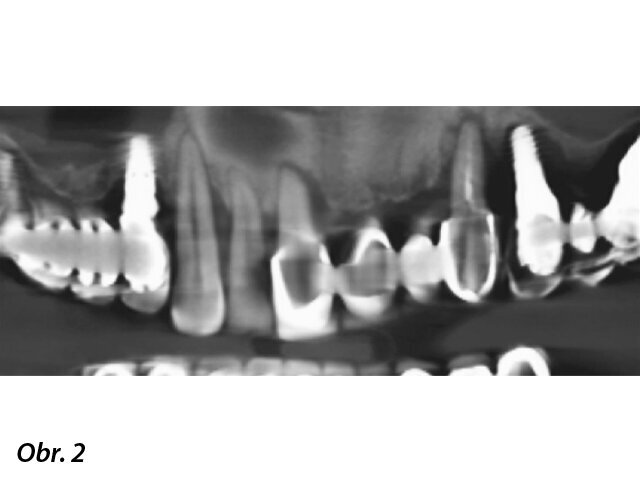

Protetické šablony byly použity ke kontrole okluze a zajištění reprodukovatelnosti.

Na základě klinických a radiologických vyšetření byly všechny zuby pacienta, stejně jako všechny implantáty v místech zubů 16 a 24, vyhodnoceny jako nezachranitelné. Naopak fixtury v místech zubů 14 a 27 byly stabilní a použitelné. Pacient nechtěl nosit v průběhu ošetření snímatelnou náhradu, a to ani po krátkou dobu. Také vyjádřil svá očekávání stran úrovně estetiky. Z tohoto důvodu bylo v rámci plánování ošetření rozhodnuto o okamžitě zatížených implantátech v obou čelistech a rehabilitaci celých úst. Poté byl zpracován diagnostický wax-up a bylo rozhodnuto v této fázi ošetření neupravovat vertikální rozměr habituální okluze pacienta. Zubní technik vyrobil dvě chirurgické šablony a dvě protetické šablony pro otiskování – tedy podle protokolu popsaného Ghirlandou a kol. Pacientovi byla podána intravenózní sedace a lokální anestezie (Scandonest 2 %, 1 : 100000 adrenalin; Septodont).11 Nejprve byly extrahovány všechny zbývající zuby a mobilní implantáty (obr. 3). Pak byly vyzkoušeny protetické šablony a zkontrolována okluze a reprodukovatelnost diagnostického wax-upu (obr. 4). Šablona pro horní čelist poté byla stabilizována na pilířích našroubovaných na stávajících implantátech.